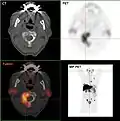

- Projection d'intensité maximale avec divers traceurs

- Projection d'intensité maximale d'un TEP/scanner avec de la choline. On reconnaît clairement l'enrichissement physiologique dans le foie, le pancréas, les reins, la vessie, larate, la moelle osseuse et les glandes salivaires. La métastase osseuse se trouve dans le pubis à gauche.

- TEP/scanner d'intensité maximale avec du fluorodésoxyglucose (18F) (FDG) avec un cancer du sein en métastases. Tumeur primaire dans le sein droit. Métastases dans les ganglions lymphatiques du médiastin et dans les poumons. Les métastases osseuses sont mieux délimitées dans la vue avec 18F-NaF (vidéo suivante).

- TEP/scanner au maximum d'intensité avec du 18F-NaF (fluorure de sodium) sur un cancer du sein en métastases dans le crâne, la colonne vertébrale, le bassin, les côtes, la clavicule gauche et le fémur droit. Même patiente que dans la vidéo précédente (FDG).

Les métastases osseuses de divers cancers peuvent être très bien visualisées par TEP/scanner. Le procédé est plus sensible que la TEMP et notablement plus que la scintigraphie, cependant, plus sophistiquée, et donc plus onéreuse. Selon de type de tumeur primitive, on utilise divers traceurs, mais le plus souvent le Fluorodésoxyglucose (18F) et le fluorure de sodium NaF (18F), et aussi pour le cancer de la prostate la choline (18F). L'activité métabolique de la tumeur est le plus souvent bien visible avec le FDG, et la réaction de l'os à la métastase avec le NaF[124].